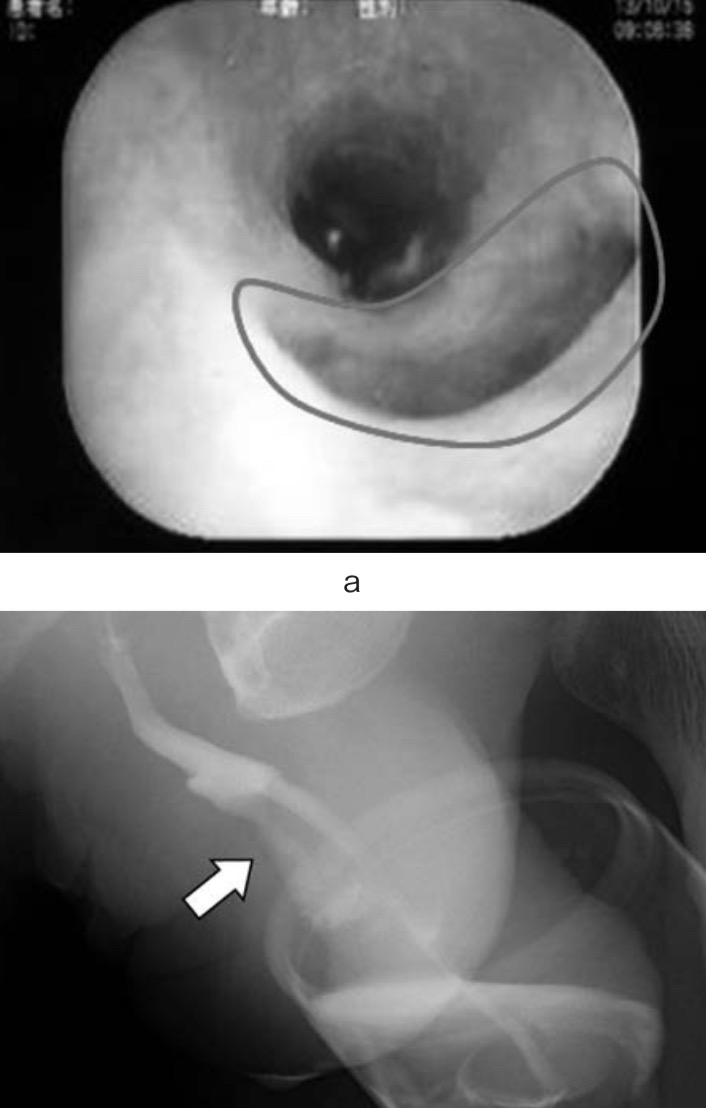

а: Уретроскопия показала кожно-уретральный свищ в передней части мочеиспускательного канала (круг).

б : цистоуретрография мочеиспускательного канала показала кожно-уретральный свищ (стрелка).